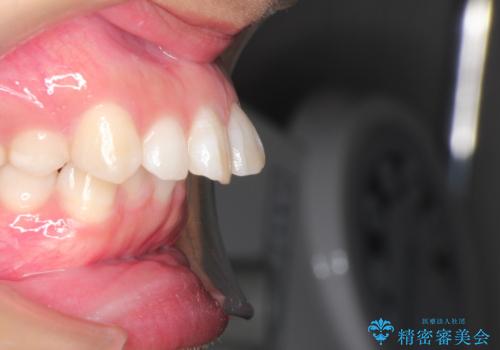

下の歯並びに対して、上の歯が全体的に前方に位置している状態でした。

上の歯の前から4番目の歯を2本抜歯して、そのスペースに前歯を移動させて、前歯を引っ込める計画としました。

抜歯をすることでしっかり前歯を後方に移動させて、引っ込めることができました。